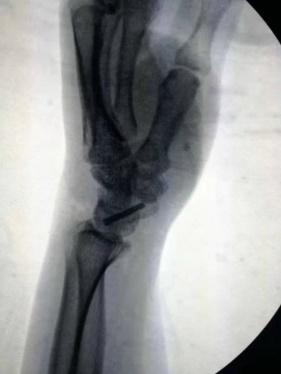

術(shù)前影像資料,舟骨腰部偏近極的骨折

四川友誼醫(yī)院骨科最近成功開展了一例“微創(chuàng)舟骨骨折空心釘固定手術(shù)”。患者曹某某,女,52歲。因“外傷致左腕關(guān)節(jié)疼痛、活動受限1小時”入院。輔助檢查:左腕關(guān)節(jié)CT平掃:左腕舟骨骨折。226日行“左腕舟骨骨折切開復位內(nèi)固定術(shù)”。術(shù)后復查骨折復位良好,內(nèi)固定穩(wěn)定可靠。左腕關(guān)節(jié)活動良好。